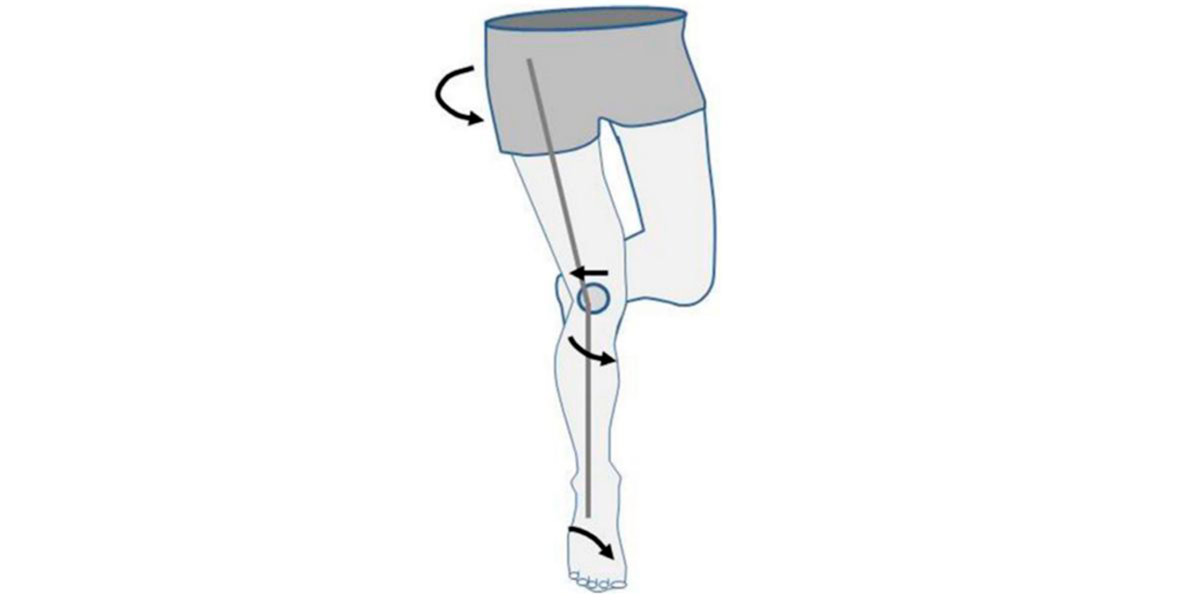

A principal manifestação do joelho é a do desvio patelar:

Este desvio verifica-se quando realizamos exercício físico, por exemplo, no denominado valgo dinâmico funcional, onde o fémur ou a tíbia (ou ambos) rodam internamente e fazem com que o joelho de desloque «para dentro» (adução);

Uma posição na qual não deveria estar, e que aumenta radicalmente a resistência por atrito, degradando a cartilagem.

Figura IV. Representação gráfica de um valgo funcional no joelho.

A articulação do joelho, que está sujeita a esta posição durante muito tempo (por exemplo, os praticantes de desporto), acaba por deslocar a rótula para o exterior, dificultando o controlo muscular sobre a articulação e causando uma grande instabilidade sobre o joelho, o que aumenta o rico de sofrer uma lesão aguda (como uma luxação ou um deslocamento), e/ou crónica (tendinite, desgaste da cartilagem, osteoartrite…).

Esta situação denomina-se de desvio patelar.